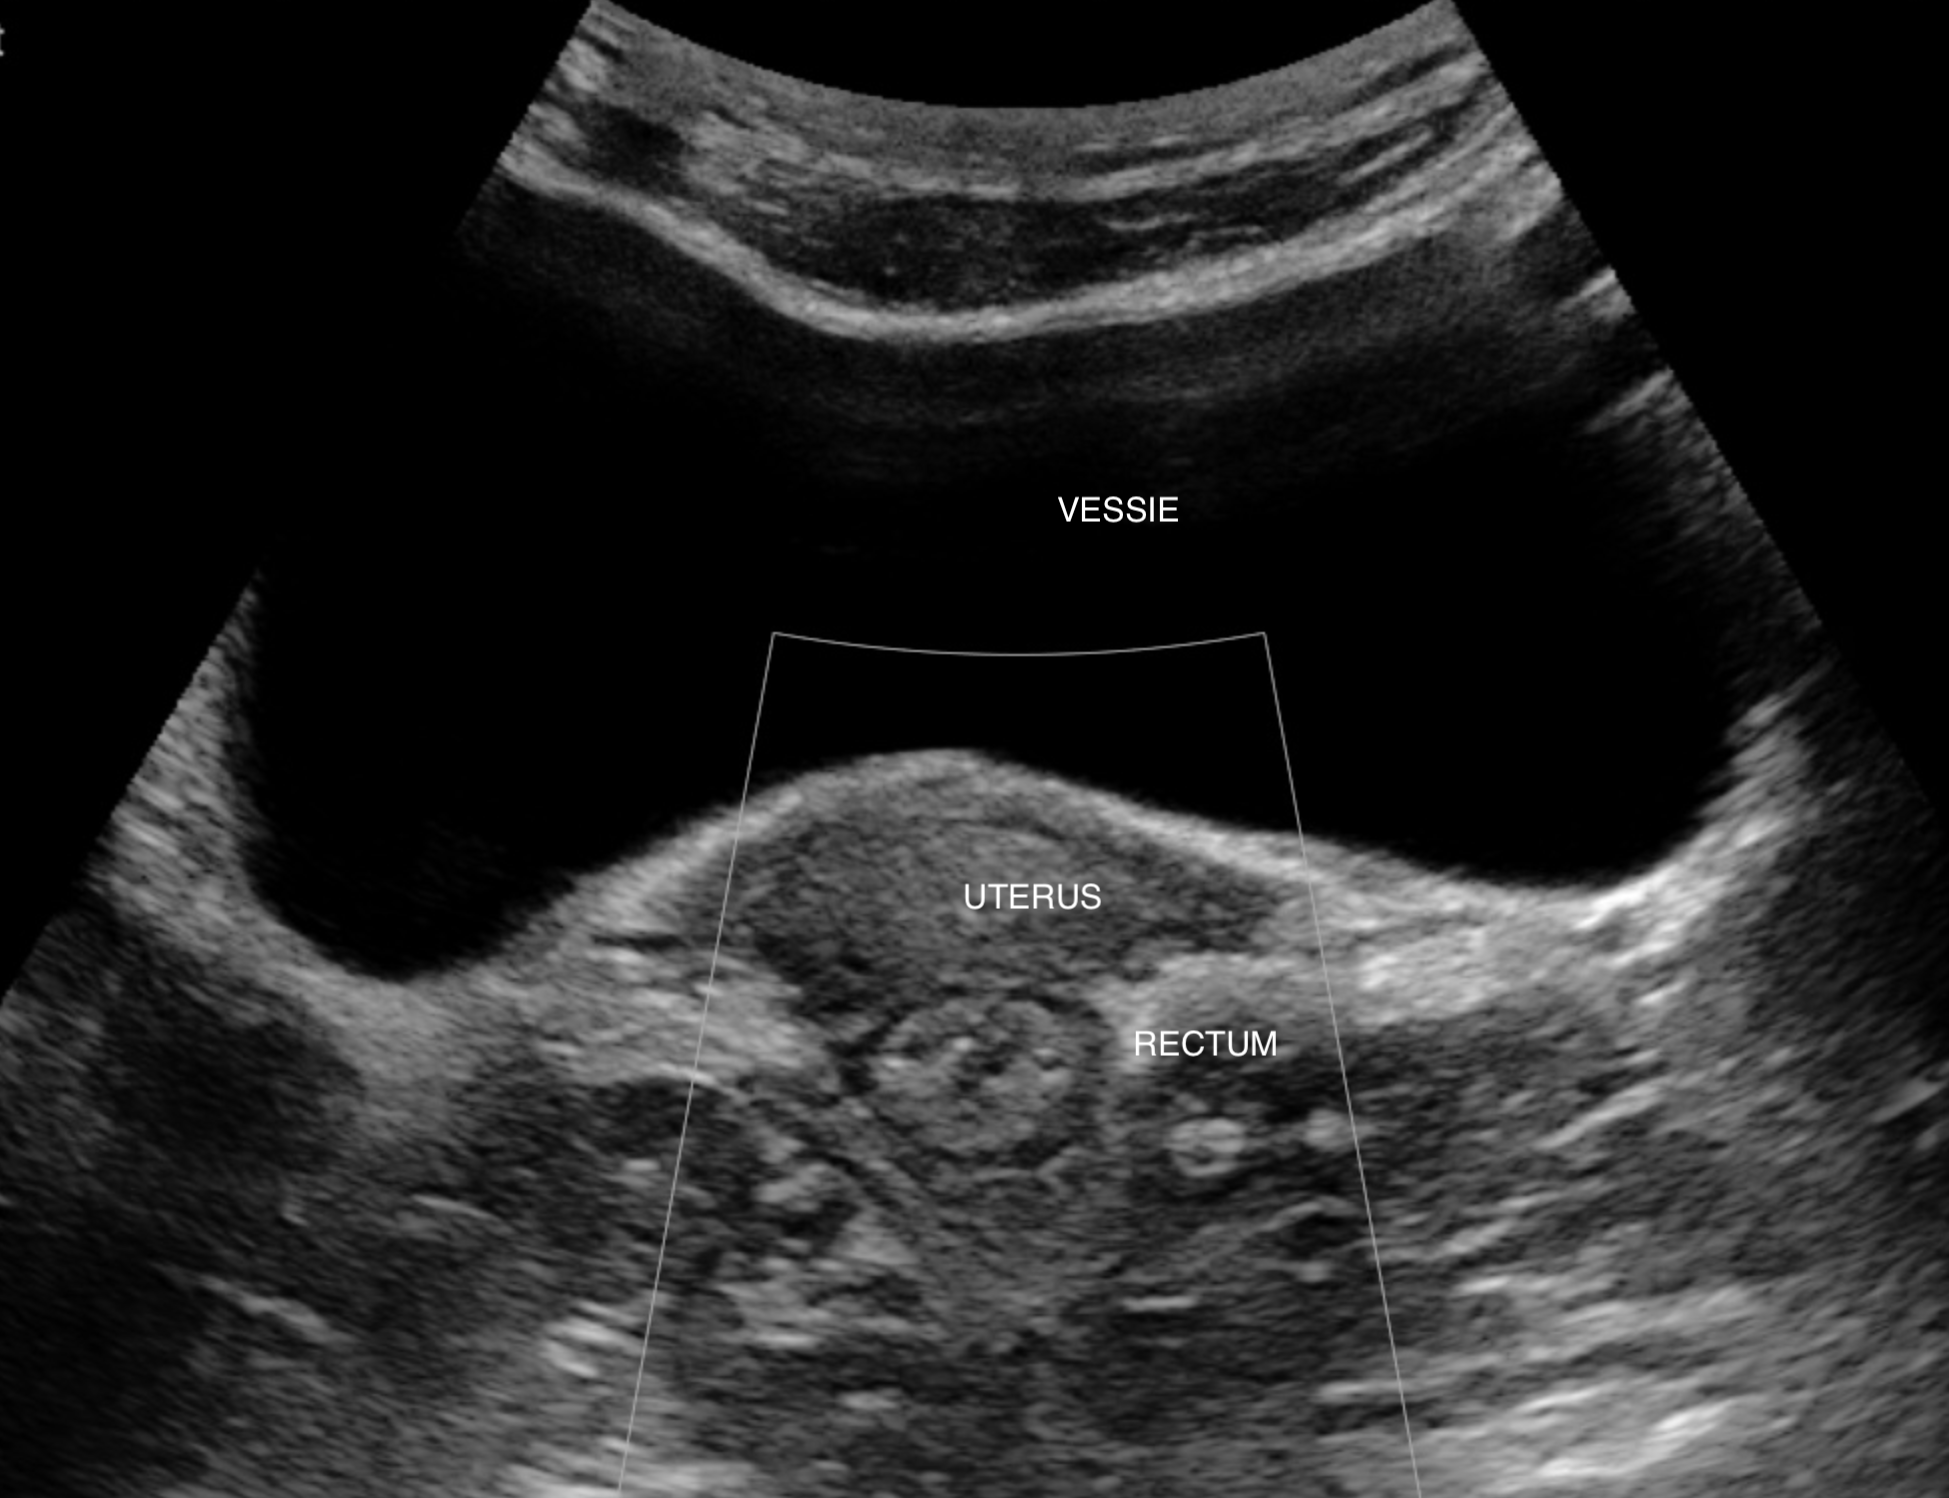

Le rectum est une des zones les moins bien vues par l'echographie, elle reste accessible

Vessie semi pleine pour améliorer la visibilité, la vessie est le repère principal

La vessie

l'axe vagin-utérus (attention à ne pas confondre la paroi du vagin avec le rectum)

Le rectum